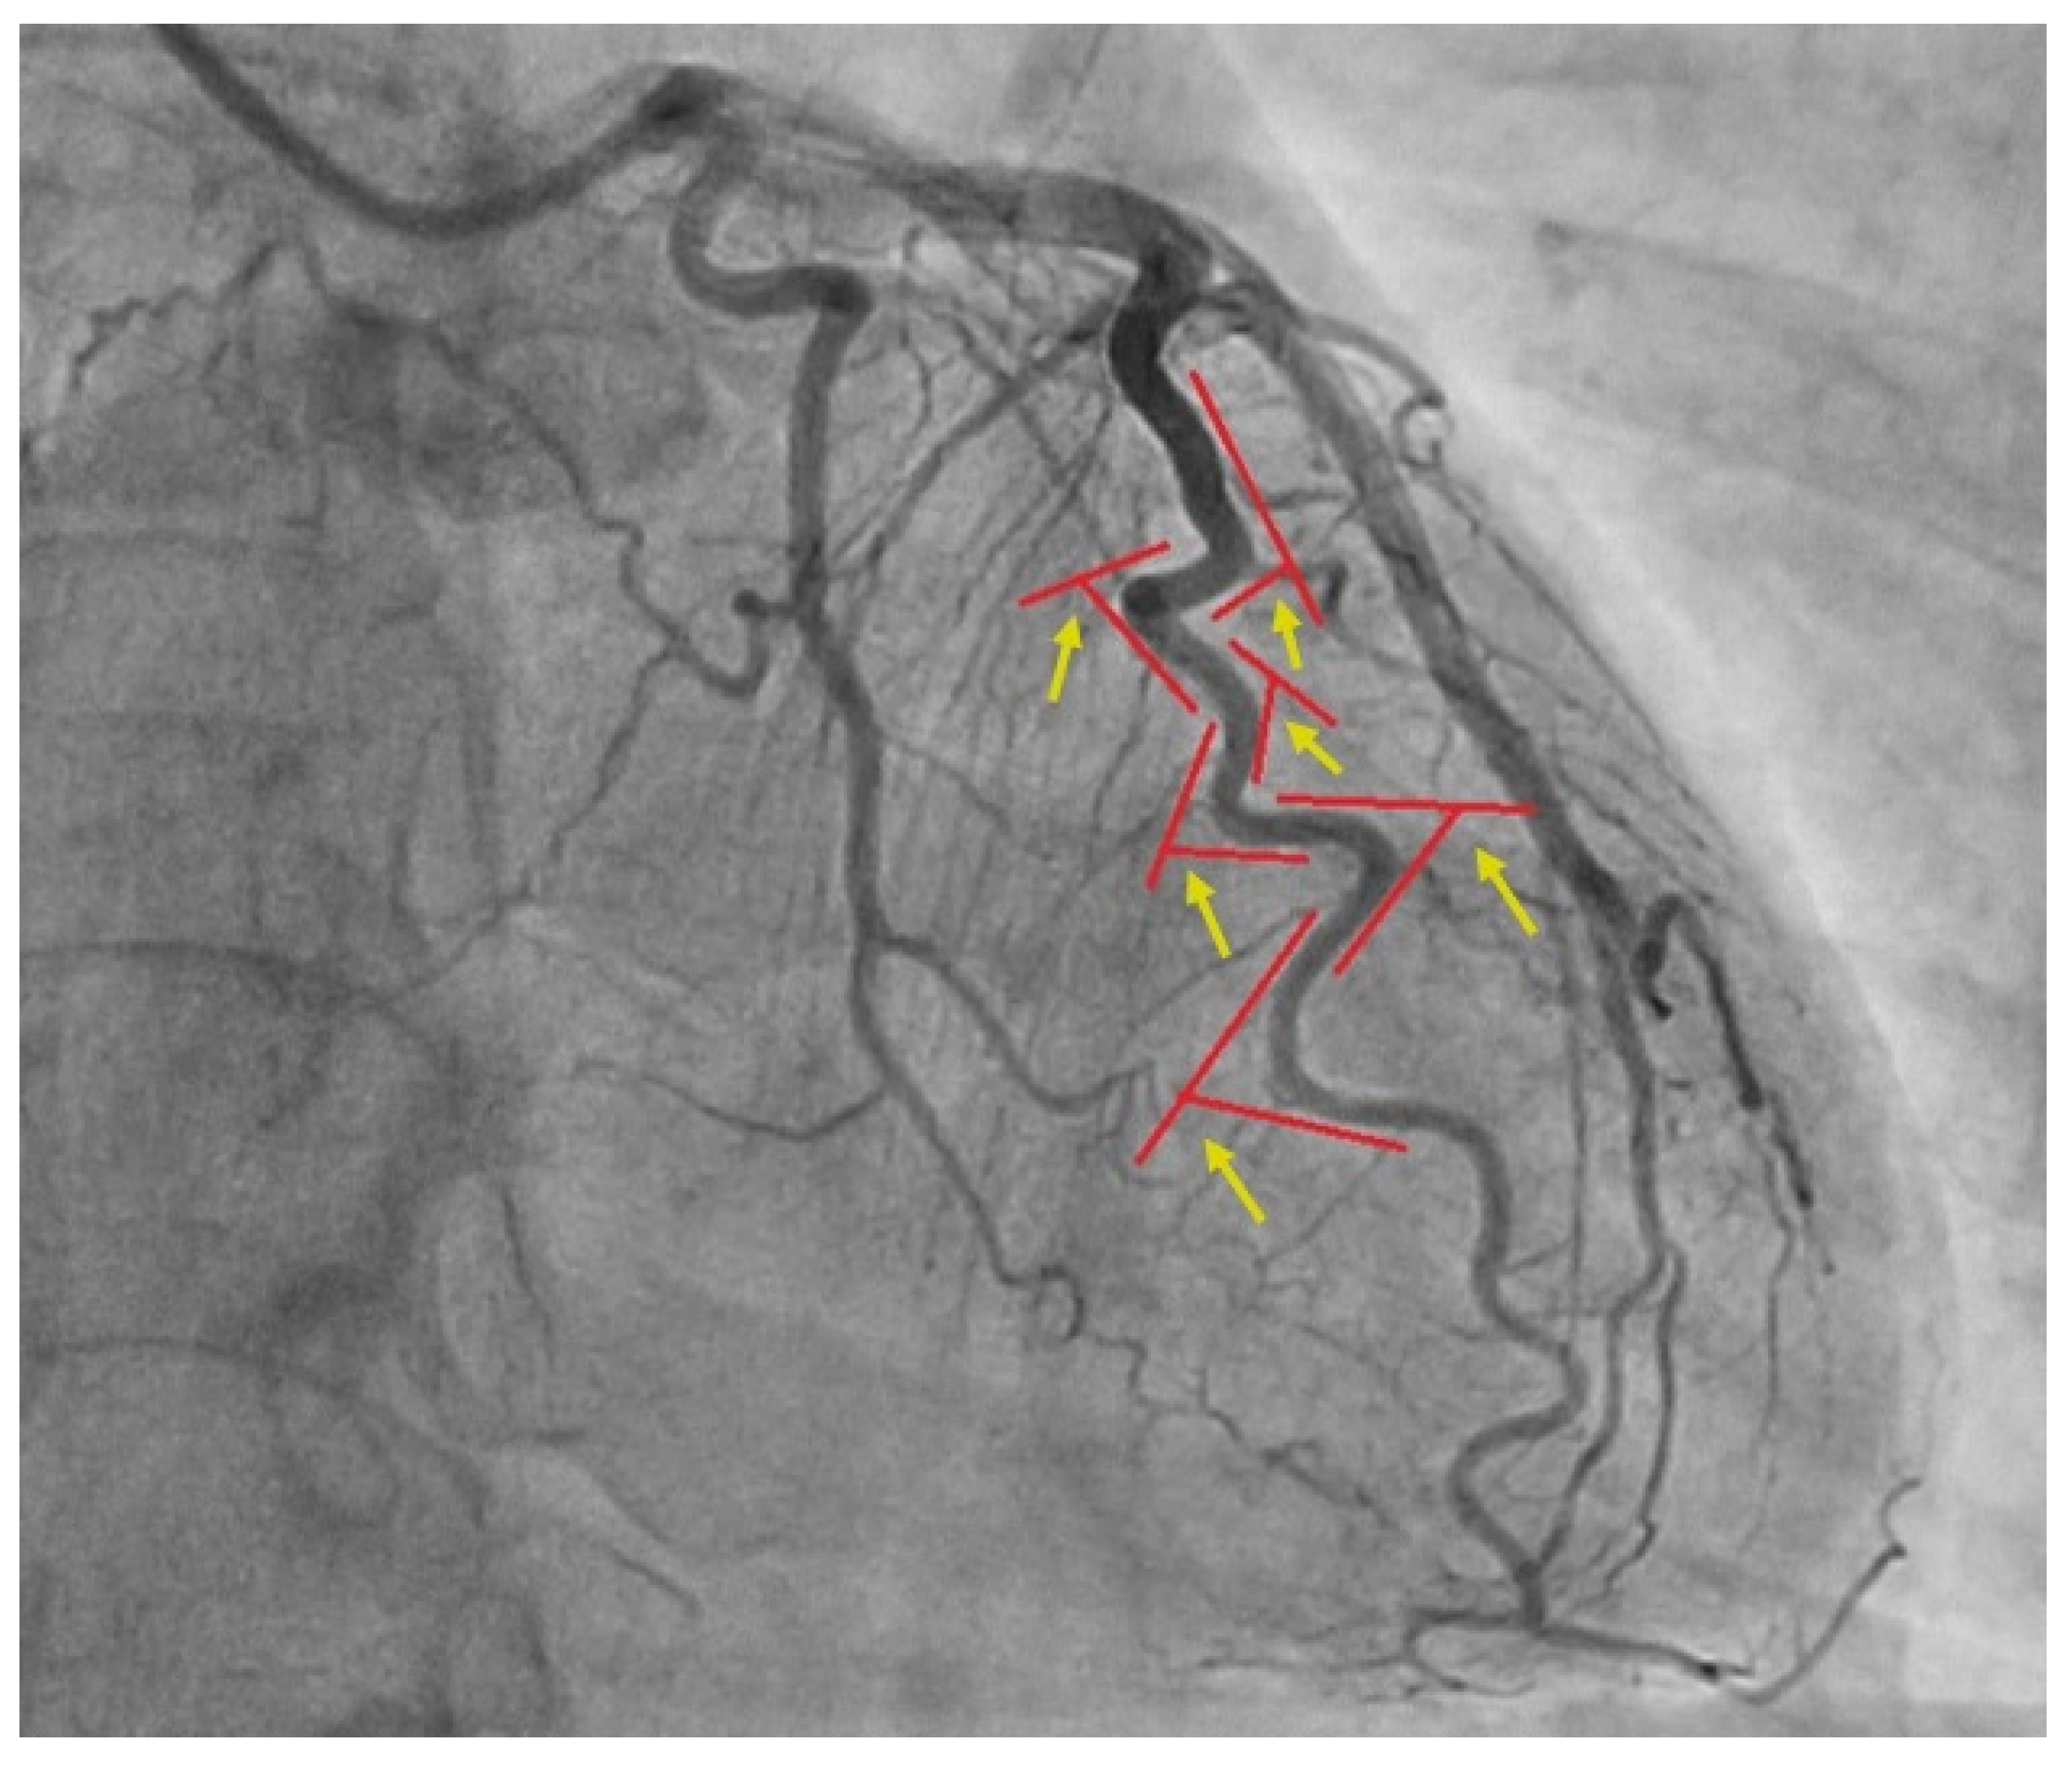

2. Materials and Methods